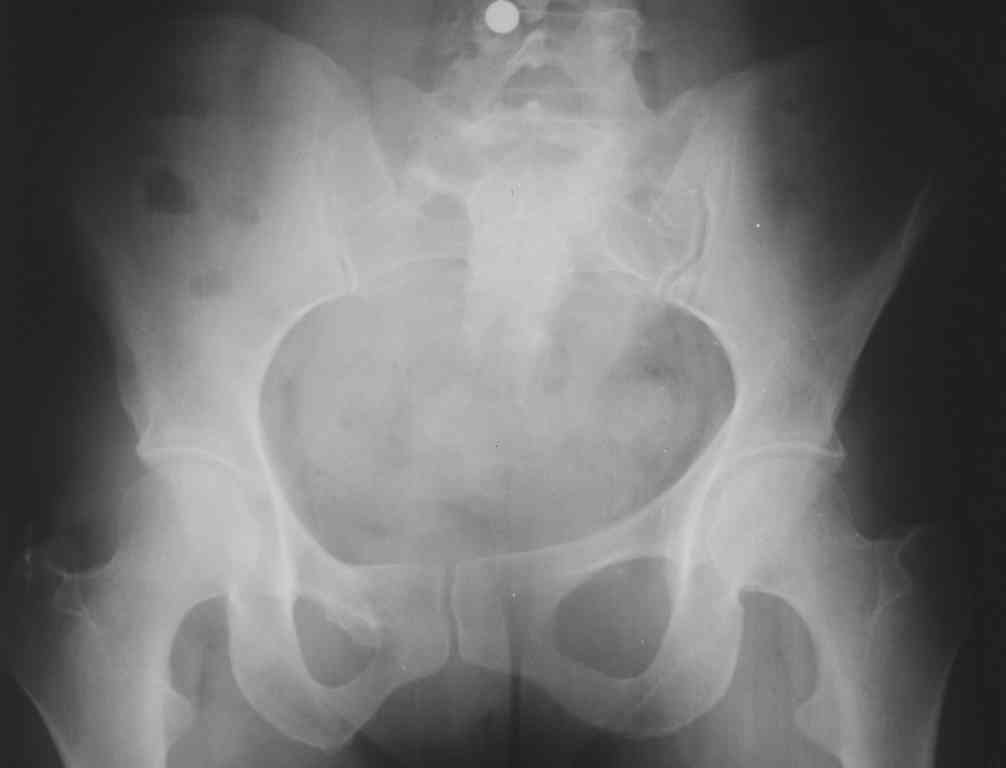

13/03/03 |  13/03/03 |  13/03/03 |  15/09/06 |  15/09/06 |  07/03/07 |  07/03/07 |  19/12/06 | К нам в клинику поступила пациентка 30 лет с диагнозом: Постравматическая ротационная стабильная деформация тазового кольца. Относительное укорочение левой н\конечности на 1 см. Левосторонний компенсаторный сколиоз 2 ст. Болевой синдром. травма автодорожная в январе 2003г. Пассажирка переднего сидения ваз 2109. лечились положением по Волковичу. С марта 2003 года жалуется на боли в тазу, ппояснице усиливающиеся при движении.В настоящее время жалобы на боли в области крестца, КПС больше слева, в пояснично-крестцовом отделе позвоночника. неприятные ощущения, щелчок при выпрямлении правого тазобедренного сустава из положения полного сгибания. боли в тазу появляются при ходьбе ч\з 100 м, так же при вставании из положения сидя, после сидения в течении 2-3 часов. при ходьбе более 100 м появпяется зябкость стоп больше справа. ходит при помощи трости в правой или в левой руке. без трости боли появляются сразу после начала ходьбы. пальпация болезненна в паравертебральных точках средне-грудного и пояснично-крестцового отделов позвоночника, КПС с обеих сторон. Объем движений в тазобедренных суставах полный.правый КПС заблокирован. симптомы натяжения с обеих сторон отрицательны.С 2003г. лечится консервативно, получала ЛФК, массаж, физиолечение - без эффекта. в 2005г. лечилась в санатории с ортопедическим уклоном, получала плавание в минеральной воде, магнитотерапия, массаж, ЛФК. отмечала умеренное улучшение в течении 2 недель.Вопросы:надо ли оперировать, т.е. устранять относительное укорочение левой н\конечности и как?Если не оперировать, то как лечить консервативно?Р-граммы, КТ прилогаются.

Проблема Вашей пациентки находится на границе интересов специальностей ортопедия (вертебралогия) и неврология (нейрохирургия), вероятно, поэтому так мало откликов на ваше обращение. Представленные рентгенограммы не все информативны (особенно спондилограммы от сентября 2006 года). Вероятно, необходимы дополнительные методы исследования к.т. МТГ, ЯМРТ, миелография.

Уважаемый Алексей. Описанные Вами клинические проявления указывают на нестабильность левого крестцово-подвздошного сочленения. Такие больные встречаются не редко (за последние 6мес.в нашей клинике оперировано 3 больных со сроками давности от 6мес. до 1 года). К сожалению рентгенологически их трудно обьективизировать. На КТ это проявляется артрозом и костными разрастаниями КПС. В Вашем случае рентгенограммы и представленные томограммы ничего не дали. Можно попробовать посмотреть связочный аппарат КПС на МРТ хотя не уверен что Вы получите окончательный ответ. Если Вы будете убеждены в этом диагнозе то выход один костно-пластический артродез левого крестцово-подвздошного сочленения с фиксацией канюлированными шурупами. Заманчиво конечно и устранить ротационное смещение половины таза, но это на Ваше усмотрение.

почему она должна возникнуть? Сломан вроде крестец, хотелось бы посмотреть функциональные снимки таза.

Уважаемый Максим. Снимки от 7.03.07 и есть функциональные, т.е. стоя на правой, и левой ноге.